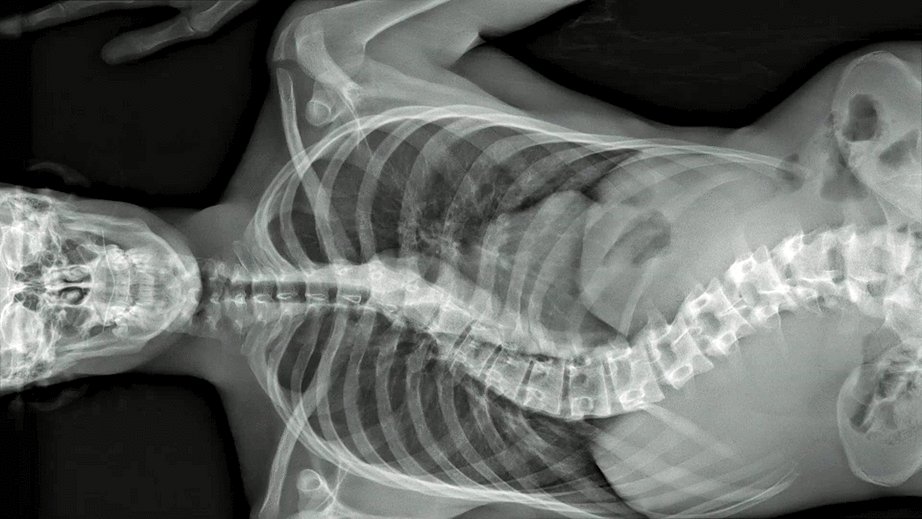

Five centuries ago, anatomist André Vésale opened up the human body to science for the first time in history. Today, De Humani Corporis Fabrica opens the human body to the cinema. It reveals that human flesh is an extraordinary landscape that exists only through the gaze and attention of others. As places of care, suffering and hope, hospitals are laboratories that connect every body in the world.